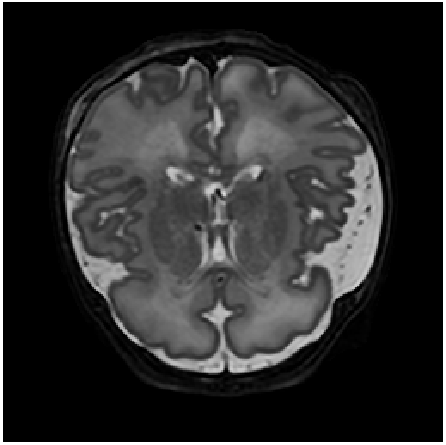

Figure 9: Zoomed-in images of synthesis results in scans of two different patients (one example per row) using neonatal brain MRIs from the dHCP dataset. Slice spacing was improved from 222 to 0.29 mmtimes0.29millimeter0.29\text{\,}\mathrm{mm} by synthesizing six intermediate slices (second to penultimate columns). For this, latent space encodings of the two neighboring slices (first and last column) were combined using their convex combination. α𝛼\alpha denotes the mixing coefficient as specified in Equation 1. Bounding boxes focus on anatomical variations between images in a row. Note that a small cross-fade artifact appears in the bright area of the fourth (α=3/7𝛼37\alpha=\nicefrac{{3}}{{7}}) and fifth (α=4/7𝛼47\alpha=\nicefrac{{4}}{{7}}) image in the second row.

Slice Synthesis: Qualitative evaluation of the proposed approach on neonatal brain MRI with reveals that generated slices using a convex combination of neighboring slice encodings, comprise a smooth anatomical transition between adjacent slices. Examples depicted in Figure 9 show upsampling performance of proposed method for neighboring slices with large anatomical variations. In the depicted figures slice spacing was improved from 222 to 0.29 mmtimes0.29millimeter0.29\text{\,}\mathrm{mm} by synthesizing six intermediate slices using latent space encodings of the two neighboring slices.